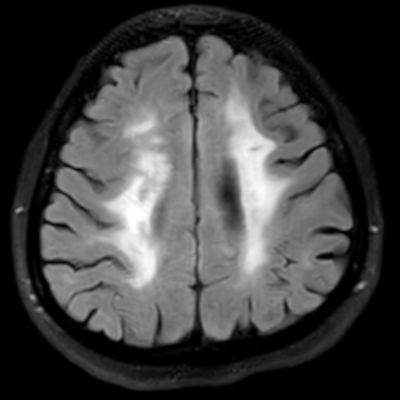

45 yaş, K

4 yıl önce akut sağ hemiparezi, konuşma bozukluğu ve dış merkezde serebellar iskemi tanısı ile ASA kullanımı öyküsü

Konuşma bozukluğu, yersiz gülme ve ağlama atakları, denge kaybı ve uyuşmaları devam ediyor

CADASIL

CADASIL SENDROMU